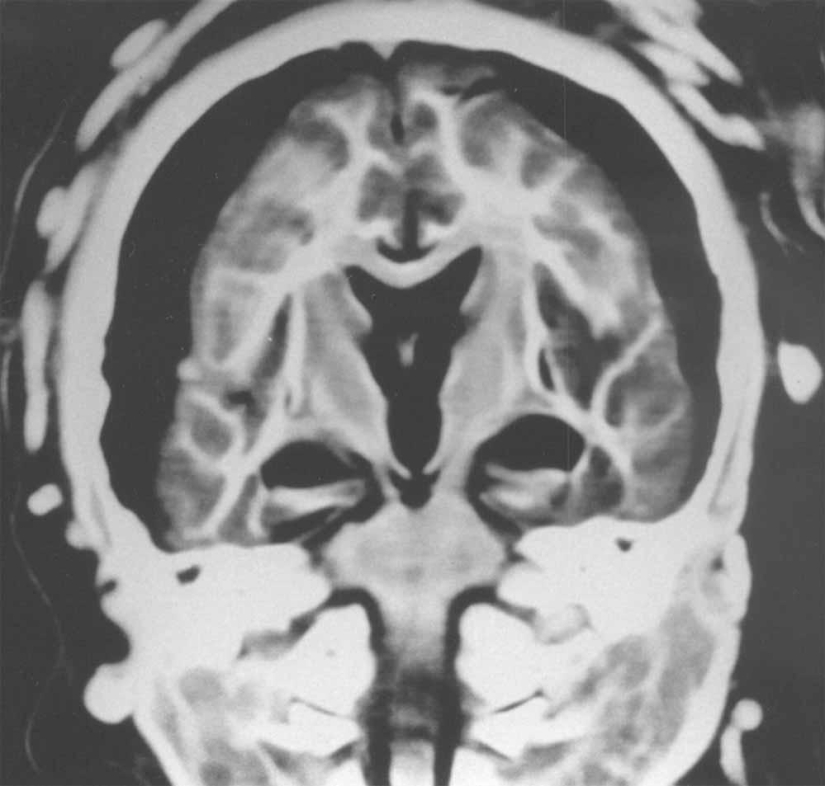

Una radiografía del cerebro de una niña de 15 años muestra que hay una separación entre la materia blanca y gris del cerebro. Las flechas apuntan al aire que rodea el cerebro.

Y esta radiografía mostró que el cerebro de un niño de 5 años estaba preservado en perfectas condiciones.